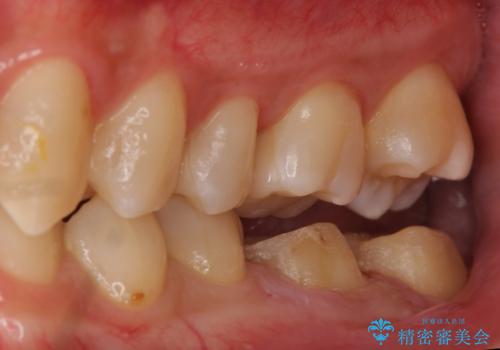

放置した虫歯の治療 親知らずの手前が虫歯

- 詰め物が取れて放置していたとのこと。

虫歯が大きかったため、被せ物(クラウン)としました。

親知らずを抜いてから治療しています。

幸い神経を取らずにすみました。